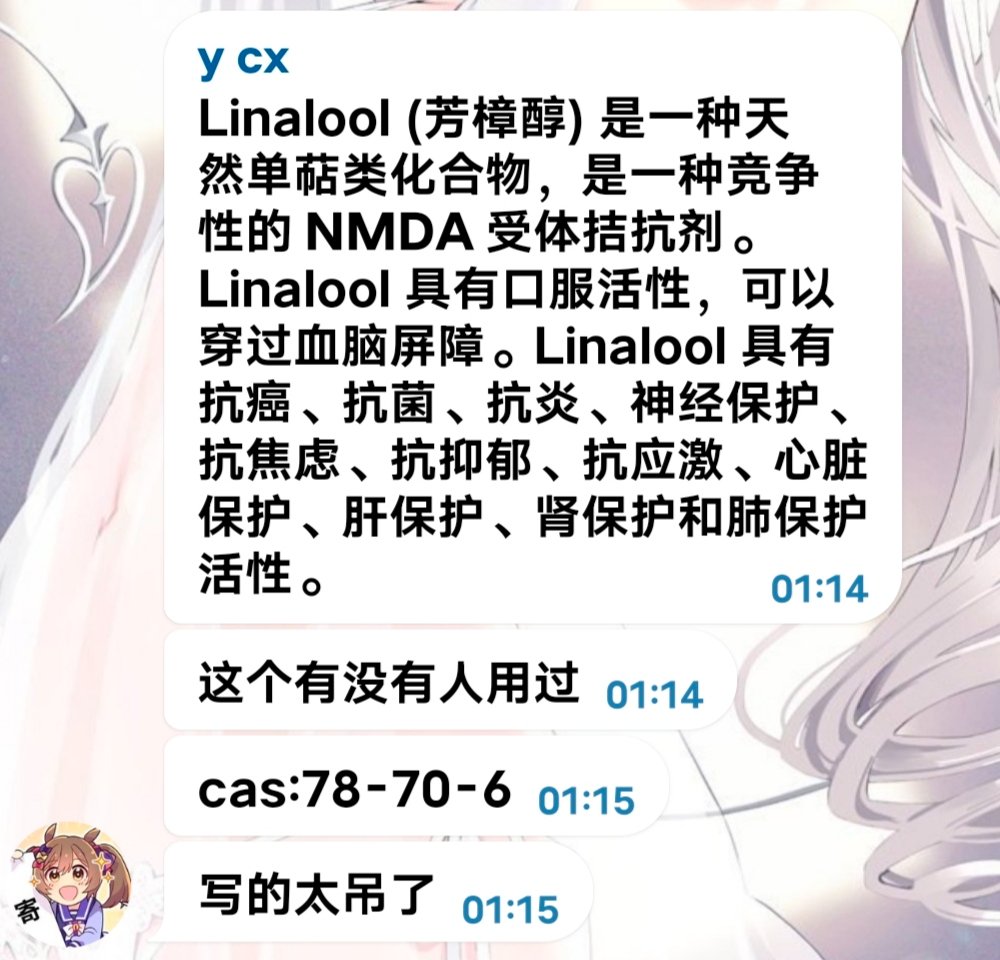

首先,从定义上讲,“反解离(anti-dissociative)”并不是一个标准的医学术语或者广泛认同的药理学分类。在正规资料,比如医学文献、维基百科、精神药理学教科书中,目前并没有“反解离药物”这个正式概念。

看上去像是为了描述某类特定效应而创造的术语(可能是nmda受体活性增强),用来对抗因NMDA受体拮抗剂(比如氯胺酮、DXM、PCP等)引发的解离体验(dissociation)。

那么更常见的是将其归入认知增强剂(cognitive enhancers),特别是改善认知连接性(connectivity)和现实感知(reality testing)的类型。

但其实在药理学上,单纯用“受体激动剂”来逆转“受体拮抗剂”的效应,有时会导致过度激活。

对于NMDA受体而言,过强的NMDA活化本身就与兴奋性毒性(excitotoxicity)和精神病样症状(psychotomimetic effects)有关,比如谷氨酸风暴可以引发严重的焦虑、妄想、乃至癫痫。

也就是说,简单地“激动-解除拮抗”在中枢神经系统是很危险的做法,尤其是对于易感个体(如有精神分裂素质的人)。

科学的处理方式一般是通过更细致的调节,比如微调NMDA/AMPA平衡、调节其他辅助途径(如GABA、5-HT、mGluR受体),而不是简单粗暴地用“NMDA增强剂”去顶回去。